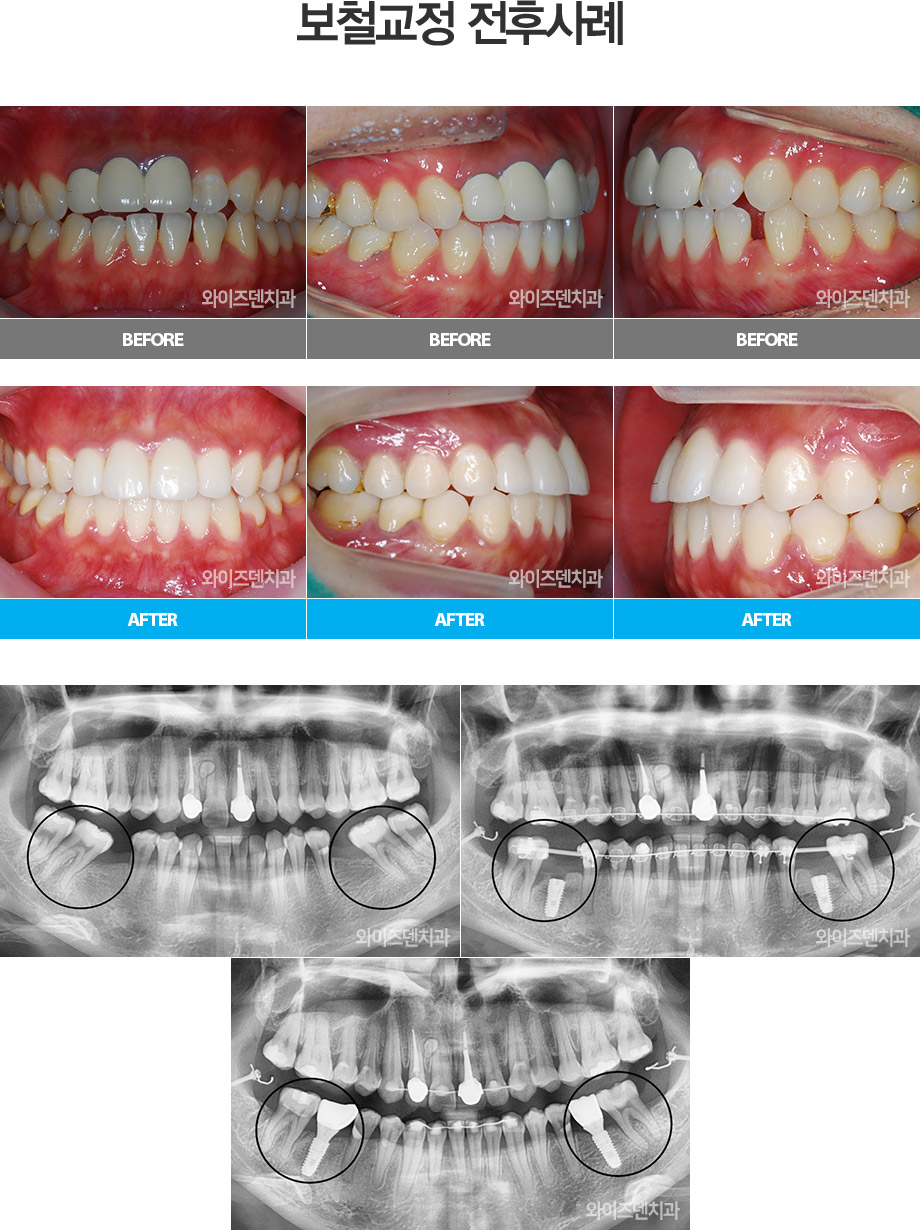

• ö